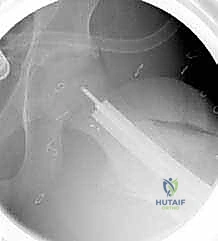

6. التثبيت الداخلي القوي (Internal Fixation)

لضمان التحام العظم في وضعه الجديد، يستخدم الدكتور هطيف نظام تثبيت عالمي يتمثل في صفيحة الشفرة الزاوية (AO 90-degree Blade Plate) أو مسامير وصفيحة مخصصة للأطفال. يتم إدخال الشفرة في عنق الفخذ، وتثبيت الصفيحة على جسم العظم باستخدام براغي معدنية قوية.